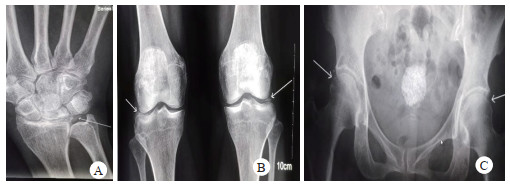

患者,女,61岁。因“阵发性心悸20余年,乏力胸闷1周余”入院。患者20余年前出现阵发性心悸,诊断为“心肌炎”,未予特殊诊治,1周余前无明显诱因出现乏力胸闷,伴头皮麻木,遂来本院就诊,查血电解质:钾2.9 mmol/L,拟“低钾血症”收入本科。既往有糖尿病病史20余年。平时服用二甲双胍及西格列汀片控制血糖,血糖控制尚可。否认服用利尿剂或其他特殊药物史;发育正常,育有1子;父母非近亲结婚,弟弟有“低血钾”病史,但未明确病因,家族其他人无类似疾病史。查体:血压138/69 mmHg,余无殊。完善检查:动脉血气分析:pH 7.48,pCO2 35.9 mmHg,HCO3 27.3 mmol/L,BE 3.3 mmol/L,Ca 0.93 mmol/L,血生化:K 2.3 mmol/L,Na 118 mmol/L,Cl 80 mmol/L,Mg 0.2 mmol/L,Ca 1.72 mmol/L,P 0.78 mmol/L,尿酸101 μmol/L,肌酐52.6 μmol/L,甲状旁腺激素:125 pg/mL(12~65 pg/mL);立位肾素活性:153.8 μIU/mL (4.4~46.1 μIU/mL)立位醛固酮:384 pg/mL (30~353 pg/mL),随机尿钙/尿肌酐:1.19(mmol/mmol)。同步24 h尿电解质:尿量2 000 mL,尿钾120.6 mmol,尿钠259.2 mmol;血渗透压:263 mosm/(kg·H2O),尿渗透压:266 mosm/(kg·H2O)。胸部CT:两肺轻度慢支伴肺气肿。心电图:窦性心律,QTc 483 ms。关节X线:双髋关节、膝关节、右腕关节间隙可见软骨钙化影(图 1),氢氯噻嗪试验结果提示:用药前后,氯离子排泄分数变化为0.951%,说明患者肾小管对氢氯噻嗪无反应,可功能诊断GS。为进一步明确诊断,对患者进行基因检测,结果提示:SLC12A3基因存在复合杂合突变:一个错义突变c.1732G > A(p.Val578Met)和一个移码突变c.1664_1668delCGCCT(p.Ser555fs),第二个突变为新发突变(图 2)。因此,诊断:(1)Gitelman综合征;(2)焦磷酸钙沉积病;(3)抗利尿激素分泌不适当综合征;(4)2型糖尿病;(5)慢性阻塞性肺疾病。入院后予口服氯化钾片每日3.0 g;口服10%氯化钠注射液每日60 mL,螺内酯片每日60 mg,碳酸钙D3片每日0.6 g,骨化三醇胶丸每日0.5 μg,静滴硫酸镁注射液每日5 g等纠正电解质紊乱的治疗。患者乏力、胸闷症状好转,出院前复查血电解质:钾4.76 mmol/L,钠133.1 mmol/L,氯95.7 mmol/L,镁0.65 mmol/L,心电图QTc缩短至407 ms。

| 图 1 关节X平片。A.右腕关节间隙(箭头所指),B.双膝关节(箭头所指),C.双髋关节(箭头所指),均可见软骨钙化影 |

镁离子可增加焦磷酸盐溶解度,也是碱性磷酸酶的重要激活物,而碱性磷酸酶可将焦磷酸盐水解成无机磷,因此低镁血症可促进焦磷酸钙结晶在关节沉积,从而导致焦磷酸钙沉积病(calcium pyrophosphate deposition, CPPD[5]。CPPD可表现为假性痛风发作,也可以无症状。该患者X线检查提示双髋、膝关节周围、右腕关节多发钙化,考虑CPPD。本患者无关节痛,考虑为无症状型CPPD。对于有关节痛GS患者,均应行关节X线检查,避免误诊为痛风、自身免疫病所导致的关节病变。该患者有低钙血症,而低钙血症是低镁血症的经典表现,低镁血症引起低钙血症的机制目前认为抑制PTH的释放或者引起骨组织对PTH的抵抗[6]。该患者PTH偏高,考虑存在PTH的抵抗而不是PTH释放减少。